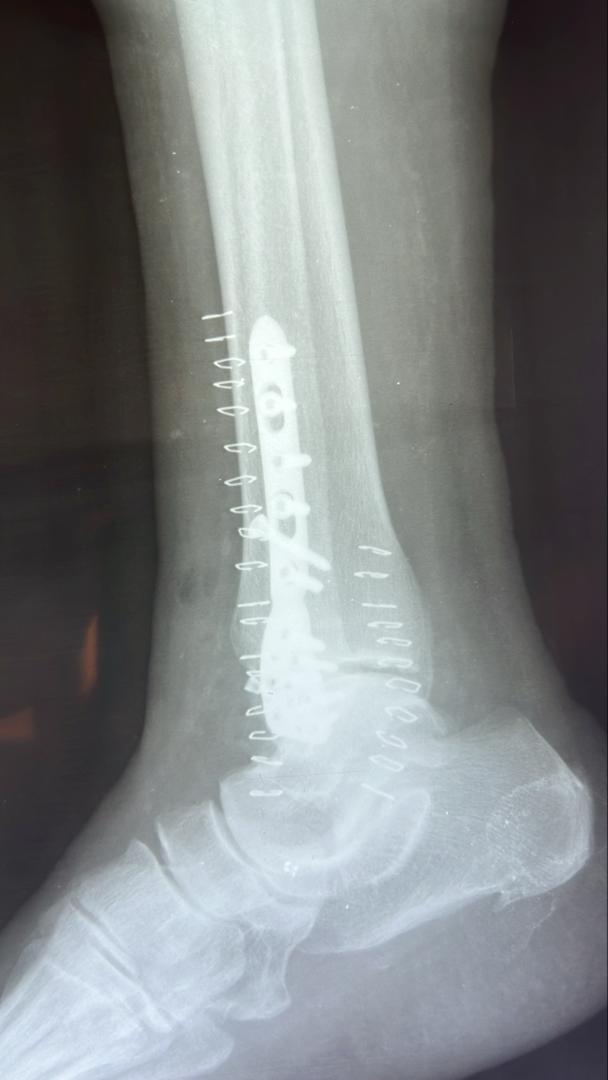

Galerie d’implants & imagerie

Exemples pédagogiques de prothèses et d’ostéosynthèses pratiquées à la CCL.

Cheville — plaque latérale